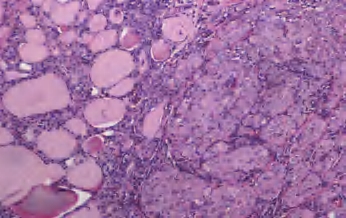

(1)嗜酸细胞亚型:此型诊断时年龄较一般滤泡癌晚10年左右,淋巴结转移率达30%,并具有更高的颈部复发倾向。大体以独特的红褐色外观为特征,镜下可见全部或大部分(>75%)由嗜酸细胞构成。肿瘤从分化很好的滤泡结构到实体性或梁状结构,含较少或缺乏胶质,核浓染,有显著的嗜酸性核仁。胶质倾向于嗜碱性且常伴同心圆钙化,一些肿瘤可有透明细胞性改变,缺乏淋巴浆细胞浸润(图3-57、图3-58)。

图3-57 右侧为甲状腺滤泡状癌,嗜酸细胞亚型;左侧为正常甲状腺组织